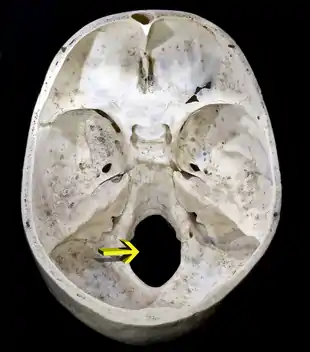

Os occipital

L'os occipital (ou l'occiput) est un os en forme de losange, taillé dans un segment de sphère, et formant la majeur partie du pôle de l'ovoïde crânienne. Il est percé d'un orifice, le foramen magnum, plus large en arrière qu'en avant et destiné au passage de l'axe cérébro-spinal, de ses enveloppes et de vaisseaux. Situé à l'arrière du crâne, il s'articule avec les os pariétaux, les os temporaux, l'os sphénoïde et l'os atlas.

On décrit sur la face interne :

- l'écaille présente la protubérance occipitale interne d'où partent :

- le sillon du sinus sagittal supérieur,

- les sillons du sinus transverse,

- la crête occipitale.

- Ces sillons délimitent deux fosses cérébelleuses et deux fosses cérébrales.

- les jonctions latérales qui supportent :

- le sillon du sinus sigmoïde,

- le foramen de l'hypoglosse.

- à l'opposé de l'écaille le clivus, rainure plate remontant vers le sphénoïde et sur laquelle repose une partie de la moelle allongée.

La moelle allongée traverse l'os occipital par le foramen magnum, qui est l'orifice de communication entre le canal vertébral et la boîte crânienne.